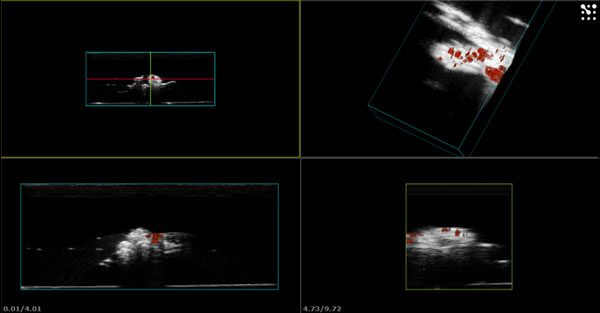

The use of ultrasound contrast agents is useful for monitoring and assisting various interventional oncology procedures including ablations and embolizations of solid tumors. We are currently using both 2D and 3D ultrasound to guide, augment, and monitor responses to these therapies. The techniques include using ultrasound contrast agents for treatment planning and probe guidance, evaluating residual vascularity post treatment, and using ultrasound-triggered microbubble cavitation to sensitize tumors to therapy.